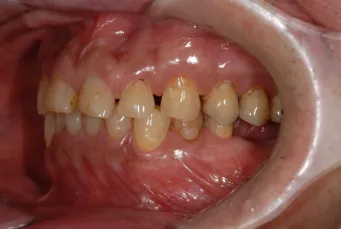

初診時

| 患者様のお悩み | 咀嚼障害、左の奥歯が抜けた。 |

|---|---|

| 治療法・使用素材 | インプラント治療の後、セラミック治療 |

| 患者様の年代 | 60代 |

| 治療開始年齢 | 60代 |

| 治療にかかった期間 | 1年6か月 |

| 性別 | 男性 |

| この治療のリスクについて | 歯ぎしりがひどいので修復物の耐久性が将来的に問題になる可能性があること |

| 治療にかかった費用 | 450万円 |